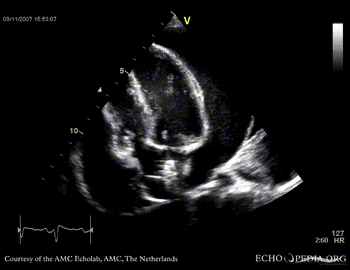

Case 14

Tamponade

Courtesy of:

J. Vleugels, AMC, The Netherlands

tamponade 2